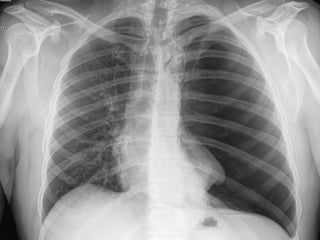

 7. Rotation

 Medial ends of

bilateral clavicles are

equidistant from the

midline or vertebral

bodies

If spinous process appears closer to the right clavicle (red arrow),

the patient is rotated toward their own left side

If spinous process appears closer to the left clavicle (red arrow),

the patient is rotated toward their own right side